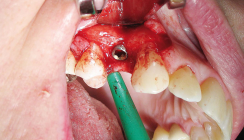

Die Operation wurde unter Lokalanästhesie durchgeführt. Ein ausreichend breiter Mukoperiostlappen wurde nach Anlegen einer leicht palatinal versetzten horizontalen Inzision durchgeführt und nach mesial auf die Regio 23 ausgeweitet. Zur besseren Zugänglichkeit des Areals wurden zusätzlich eine vertikale Entlastungsinzision zwischen 22 und 23 und eine Periostschlitzung für einen spannungsfreien Wundverschluss durchgeführt. Die Empfängerstelle wurde von Granulationsgewebe gesäubert. Abbildung 4 zeigt das durchgehend dünne Knochenangebot in Regio 24 sowie das ausgeprägte Knochendefizit in Regio 26 und 27.

Die Zähne 26 und 27 wurden extra­hiert. Der Bone Splitting in Regio 24 wurde mithilfe einer minimalinvasiven Schnittführung durchgeführt (Abb. 5). Hierzu bieten sich geeignete diamantierte Scheiben oder Piezosurgery-Ins­trumente an. Um die Lateralisierung der Knochenlamelle besser steuern zu können sowie eine unkontrollierte Fraktur zu vermeiden, wurden neben der krestalen Inzision zusätzlich zwei vertikale Frakturlinien gesetzt. Es wurden drei Implantate in Regio 24 sowie in möglichst bukkaler Position der Ex­traktionsalveolen 26 und 27 gesetzt. Ein Zugang zum Sinus mithilfe der Präparation eines Knochenfensters in Regio 26 wurde geschaffen (Abb. 6).